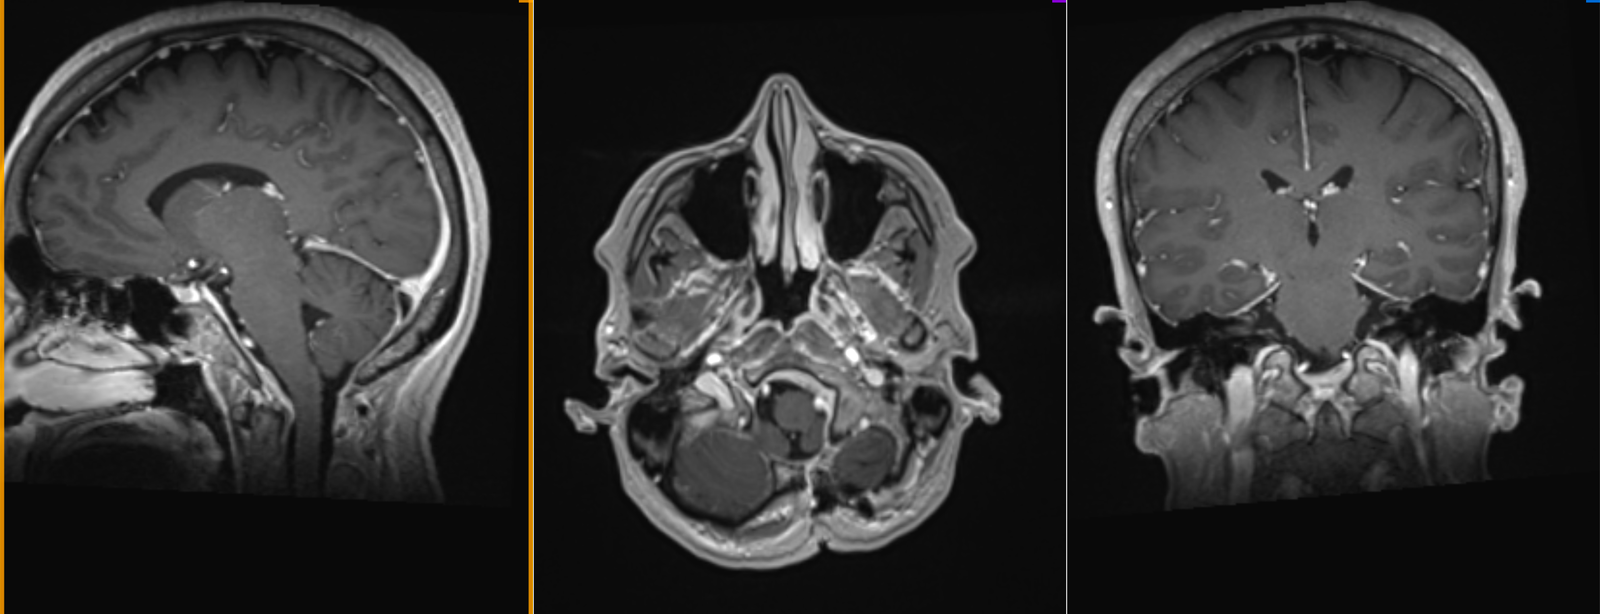

Este vorba despre o doamnă de 56 ani care a efectuat un RMN cerebral pentru a investiga un episod de pierdere a conștienței (care s-a dovedit a fi doar o lipotimie) și a descoperit că este purtătoarea unui meningiom de foramen magnum.

Tumora are baza de inserție largă pe dura mater antero-laterală stângă a joncțiunii cranio-spinale (foramen magnum) – antero-lateral stânga de trunchiul cerebral – este parțial calcificată, are dimensiuni de 36/29/31 mm și înglobează artera vertebrală stângă; la polul inferior este în contact cu nervul hipoglos (nervul cranian XII, care asigură inervația motorie a limbii); nervul spinal accesor (nervul cranian XI), care deservește mușchii trapez și sterno-cleido-mastoidian, trece pe fața posterioară a tumorii, iar nervii vag și hipoglos (nervii cranieni IX și X, care acționează mușchii laringelui și ai faringelui, esențiali pentru fonație și deglutiție) se află la polul superior al tumorii. Toate aceste contacte cu vase și nervi fac extrem de delicată intervenția chirurgicală, orice gest greșit putând avea consecințe grave pentru pacient. pe de altă parte, chiar dacă (bănuim) este vorba de o tumoră benignă, ea va crește în dimensiuni și va ajunge să înglobeze complet vasele de sânge și nervii din jur, punând presiune și pe trunchiul cerebral. În asemenea cazuri, cu cât faci operația mai repede, cu atât este mai bine pentru pacient (și pentru chirurg).